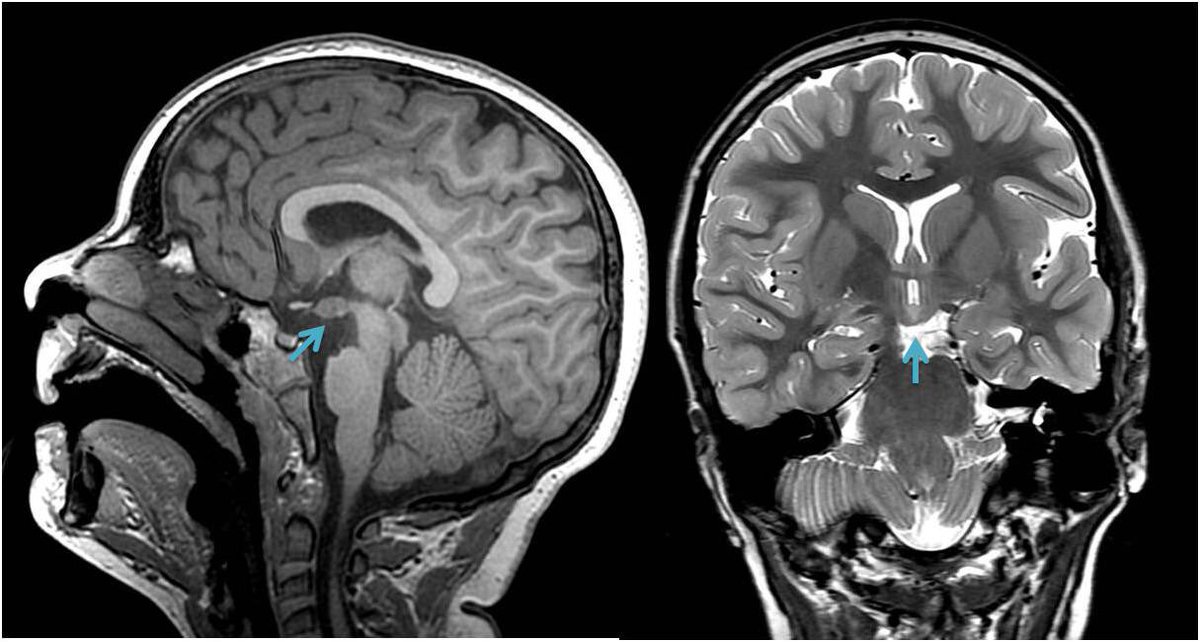

El hamartoma hipotalámico es una causa de epilepsia, cuya manifestación más típica son las crisis de risa o crisis “gelásticas”. Aquí vemos un ejemplo en RM (flecha): en corte sagital T1 (izquierda) y coronal T2 (derecha). #Epiteca #Neuroteaching #epilepsyawareness

EpilepsiaRuber's tweet image. El hamartoma hipotalámico es una causa de epilepsia, cuya manifestación más típica son las crisis de risa o crisis “gelásticas”. Aquí vemos un ejemplo en RM (flecha): en corte sagital T1 (izquierda)  y coronal T2 (derecha).